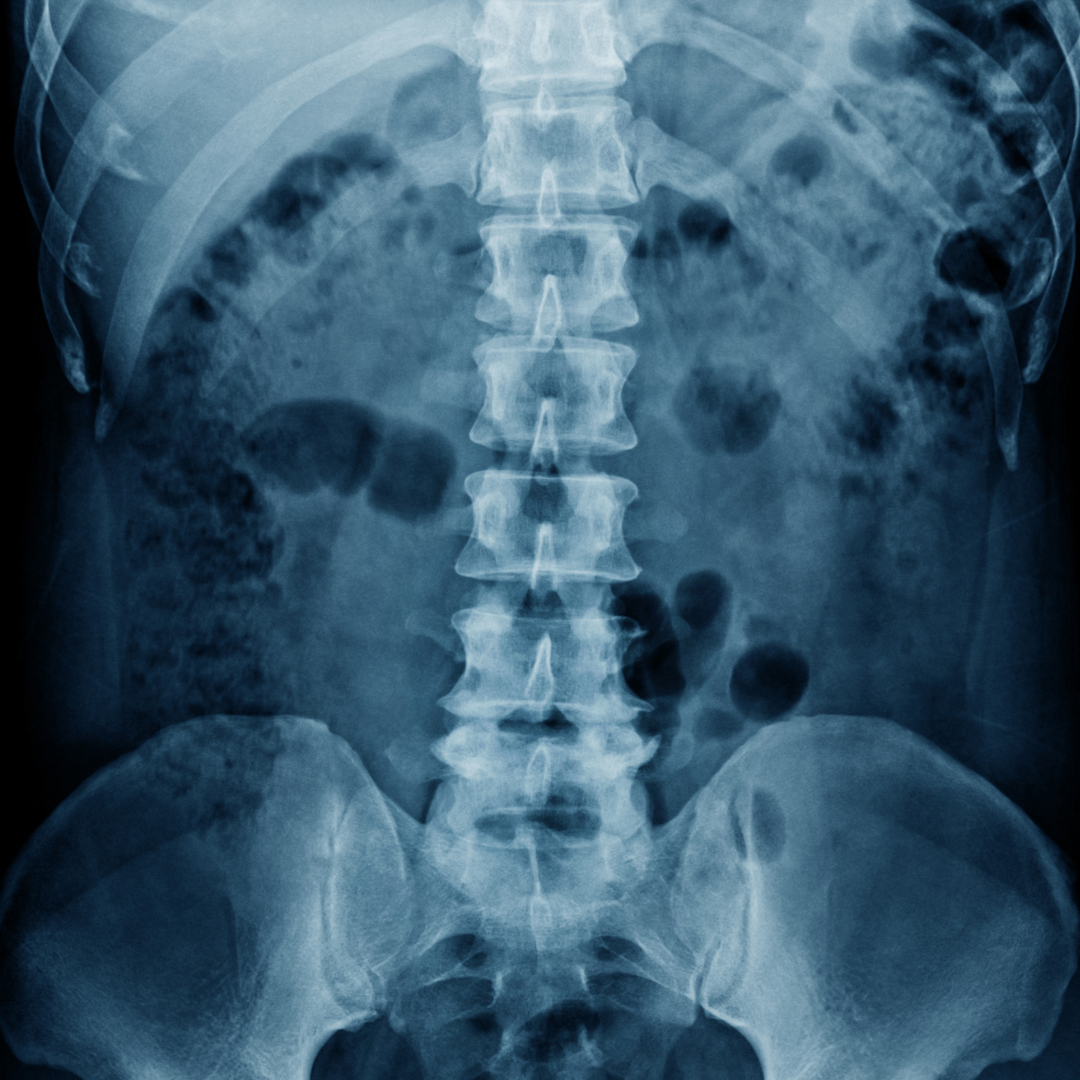

At Lopez Chiropractic in Shelby, NC, we specialize in evaluating and treating auto accident injuries with safe, non-invasive chiropractic care. Dr. Luis Lopez uses in-house digital X-rays and full-spine assessments to identify misalignments, muscle tension, or nerve irritation caused by the impact.

At Lopez Chiropractic in Shelby, NC, we understand how these injuries develop and how to detect them early. With in-house digital X-rays and a full-spine assessment, we can pinpoint the source of your symptoms—even if they haven’t fully surfaced yet—and create a plan to help your body heal properly.

At Lopez Chiropractic in Shelby, NC, Dr. Luis Lopez uses detailed spinal evaluations and in-house digital X-rays to uncover these often-overlooked injuries. By identifying the root cause early, we can help you avoid chronic pain and long-term damage.

Each treatment plan is guided by your exam results and digital X-rays, so care is always specific to your needs. Whether you’re dealing with neck pain, lower back stiffness, or nerve irritation after a crash, we’ll help you recover fully—not just feel better temporarily.

Our advanced imaging system provides clear, low-radiation images to help us detect structural problems that may not be visible from the outside.

In-House Digital X-Rays

Yes. At Lopez Chiropractic in Shelby, NC, we perform in-house digital X-rays as part of your initial evaluation. This gives Dr. Lopez a clear picture of any structural issues and helps guide your personalized care plan.

If you’ve been in a car accident—recently or even months ago—it’s important to get checked for hidden injuries. At Lopez Chiropractic, Dr. Luis Lopez offers thorough evaluations, including in-house digital X-rays, and personalized care designed to help your body heal the right way.